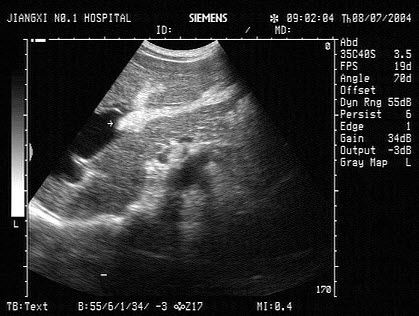

9、单项选择题

男,有胃癌手术史。根据超声声像图诊断为()

A.脾梗死

B.脾淋巴肉瘤

C.脾错构瘤

D.脾转移性癌

E.脾血管瘤